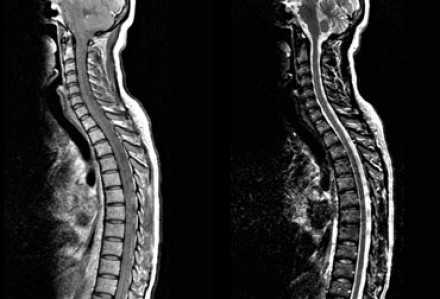

На представленных МР-томограммах патологических участков в спинном мозге не выявлено.

У пациентов, страдающих васкулитами или ишемическими заболеваниями, спинной мозг обычно не изменен, в то время как у пациентов с рассеянным склерозом в более чем 90% случаев обнаруживаются патологические нарушения в спинном мозге. Если дифференциальная диагностика очагов сосудистого характера и рассеянного склероза затруднительна, например, у пожилых пациентов с подозрением на РС, может быть полезна МРТ спинного мозга.